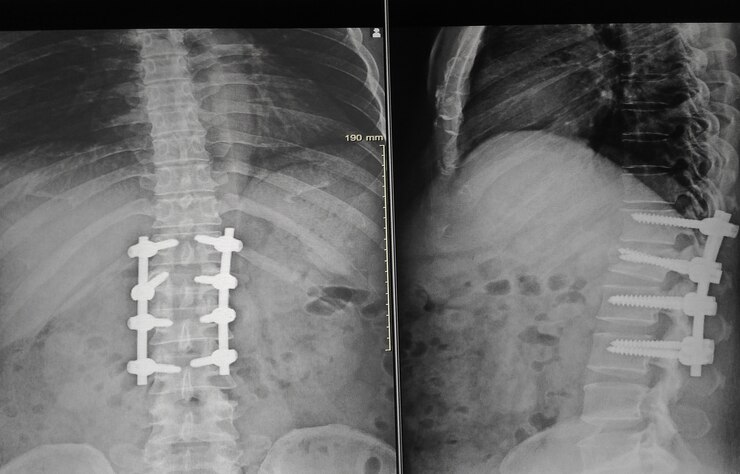

This image have hot spots where are focus is specific zone such as:

1. Lumbar Vertebrae

2. Incertion of Screw vertrebrae

3. Disck interbetebrae

4. Lung

5. Hip